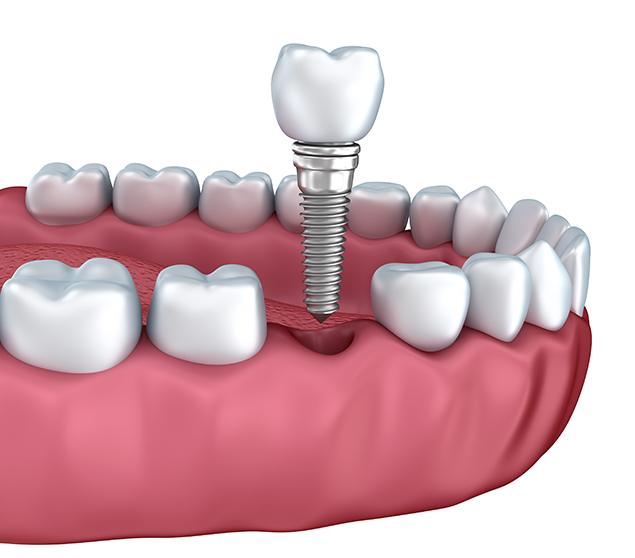

Dental implant treatment involves several steps, including planning, placement, healing, and restoration. The process and timeline vary depending on individual factors such as bone health and the number of teeth involved.